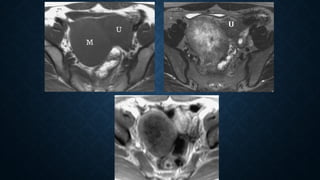

• #27 Figure 22c.  Fibroma in a 53-year-old woman. (a)Conventional radiograph shows dense amorphous calcification in the pelvic cavity. The initial diagnosis was leiomyoma with dystrophic calcification. (b) Axial turbo spin-echoT1 ) shows a well-defined round mass (M) with extensive low-signal-intensity foci representing calcifications. U = uterus. (c) On an axial turbo spin-echo T2, the mass (arrows) has low signal intensity with high-signal-intensity foci. A small amount of ascites is present in the cul-de-sac ().

• #28 Figure 23a.  Fibrothecoma in a 46-year-old woman. (a) Axial turbo spin-echo T1 shows a round, low-signal-intensity mass (M) in the right adnexal region. U = uterus. (b) On an axial turbo spin echoT2 the mass again demonstrates low signal intensity, with central increased signal intensity that represents edema. U = uterus. (c)Gadolinium-enhanced fat-suppressed T1-weighted MR image (147/4.8) demonstrates peripheral enhancement of the mass with a central edematous area.